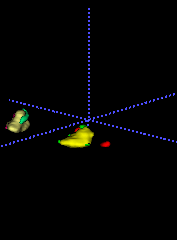

In Chapter 6, we propose an end-to-end, atlas-free 3D convolutional deep learning framework for fast and fully automated whole-volume HaN anatomy segmentation [115]. Our deep learning model, called AnatomyNet, segments OARs from head and neck CT images in an end-to-end fashion, receiving whole-volume HaN CT images as input and generating masks of all OARs of interest in one shot. AnatomyNet is built upon the popular 3D U-net architecture, but extends it in three important ways: 1) a new encoding scheme to allow auto-segmentation on whole-volume CT images instead of local patches or subsets of slices, 2) incorporating 3D squeeze-and-excitation residual blocks in encoding layers for better feature representation, and 3) a new loss function combining Dice scores and focal loss to facilitate the training of the neural model. These features are designed to address two main challenges in deep-learning-based HaN segmentation: a) segmenting small anatomies (i.e., optic chiasm and optic nerves) occupying only a few slices, and b) training with inconsistent data annotations with missing ground truth for some anatomical structures. We collect 261 HaN CT images to train AnatomyNet, and use MICCAI Head and Neck Auto Segmentation Challenge 2015 as a benchmark dataset to evaluate the performance of AnatomyNet. The objective is to segment nine anatomies: brain stem, chiasm, mandible, optic nerve left, optic nerve right, parotid gland left, parotid gland right, submandibular gland left, and submandibular gland right. Compared to previous state-of-the-art results from the MICCAI 2015 competition, AnatomyNet increases Dice similarity coefficient by 3.3% on average. AnatomyNet takes about 0.12 seconds to fully segment a head and neck CT image of dimension , significantly faster than previous methods. In addition, the model is able to process whole-volume CT images and delineate all OARs in one pass, requiring little pre- or post-processing. We demonstrate that our proposed model can improve segmentation accuracy and simplify the auto-segmentation pipeline. These contributions are released as an open-source software package called AnatomyNet, which is publicly available555https://github.com/wentaozhu/AnatomyNet-for-anatomical-segmentation. Portions of this chapter were published as part of [115].